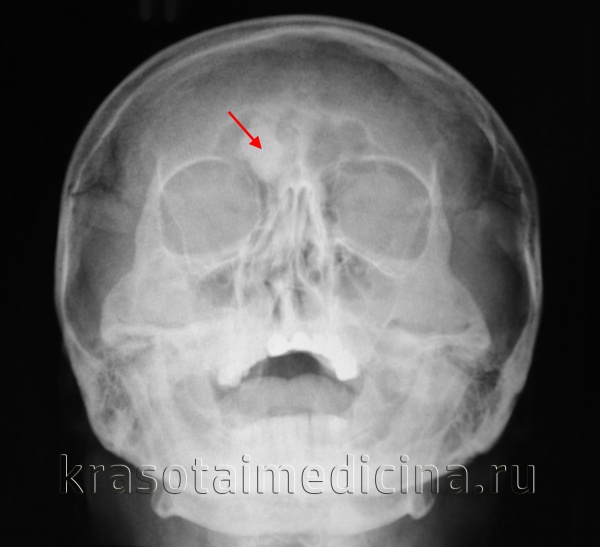

Основной способ диагностики – рентгенография. На снимке это будет выглядеть как однородная по структуре округлая опухоль с четкими границами. Остеоидная остеома на снимке представляет собой нечеткий дефект – очаг деструкции.

- Рентгенография позволяет узнать: месторасположение остеомы в кости, строение опухоли, степень деструкции кости, на которой находится новообразование, – а также определить, единичная опухоль или это множественное разрастание.

- Доброкачественность опухоли подтверждается медленным ростом, правильной структурой и геометрией, четким контуром, минимальным обызвествлением.

- При очень маленьких остеомах рентгенография не информативна, поэтому проводится компьютерная томография, позволяющая визуализировать малейшие детали структуры опухоли и замерить размеры деструкции.

Диагноз остеомы выставляется на основании дополнительных исследований. На начальном этапе выполняется рентгенография. Однако такое исследование не всегда эффективно из-за небольших размеров остеом и особенностей их расположения (например, на внутренней поверхности костей черепа). Поэтому основным методом диагностики часто становится более информативная компьютерная томография.

Диагноз остеоидной остеомы выставляется на основании характерной рентгенологической картины. Обычно из-за своего расположения такие опухоли лучше видны на рентгеновских снимках по сравнению с обычной остеомой. Однако в ряде случаев также возможны затруднения из-за малого размера остеоидной остеомы или ее локализации (например, в области позвонка). В таких ситуациях для уточнения диагноза используется компьютерная томография.

В ходе рентгенологического исследования под кортикальной пластинкой выявляется небольшой округлый участок просветления, окруженный зоной остеосклероза, ширина которой увеличивается по мере прогрессирования заболевания. На начальном этапе определяется четко видимая граница между ободком и центральной зоной остеомы. В последующем эта граница стирается, так как опухоль подвергается обызвествлению.